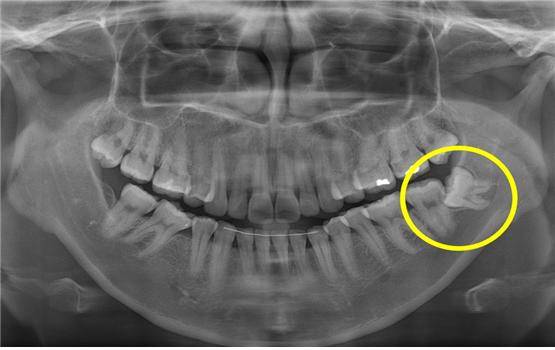

사랑니가 문제가 되는 주된 이유는 턱뼈가 작아져 사랑니가 자리 잡을 공간이 부족해지다보니, 잇몸 속에 매복돼 있거나 일부만 나오거나, 정상적인 위치에 나오지 않는 경우가 많기 때문이다. 사랑니에 대한 궁금증을 서울대치과병원 방강미 교수(구강악안면외과 전문의)의 도움말로 풀어본다.

사랑니가 잇몸 속에 완전히 매복되어 있다면, 염증을 일으키거나 주변 치아를 손상시키지는 않지만, 언제든지 문제를 유발할 수 있기 때문에 발치하는 것이 좋다. 대표적인 문제로는 매복사랑니 주위로 물혹이 발생하는 함치성낭종을 들 수 있다. 초기에는 별다른 자각증상이 없기 때문에 모르고 지내는 경우가 대부분이지만 점차 낭종이 커지면 신경손상 가능성이 증가하고, 치조골 결손이 많아지면서 치아의 위치가 변하거나 약한 충격에도 턱뼈가 부러질 수도 있다. 사랑니가 나오기 시작하는 18세 전후로는 특별한 통증이 없고, 육안으로 사랑니가 보이지 않더라도 치과에서 검진을 받아보는 것이 좋다. 사랑니가 있는 것이 확인되면 바로 발치하는 것을 추천하지만, 발치하지 않고 남겨두는 경우에는 치과에 주기적으로 방문하여 병적인 변화여부를 관찰하는 것이 좋다.